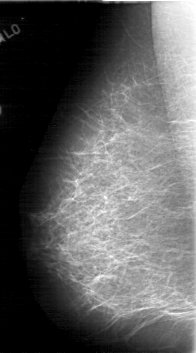

D_4083_1.LEFT_MLO

LEFT_MLO LINES 5386 PIXELS_PER_LINE 3091 BITS_PER_PIXEL 12 RESOLUTION 43.5 OVERLAY